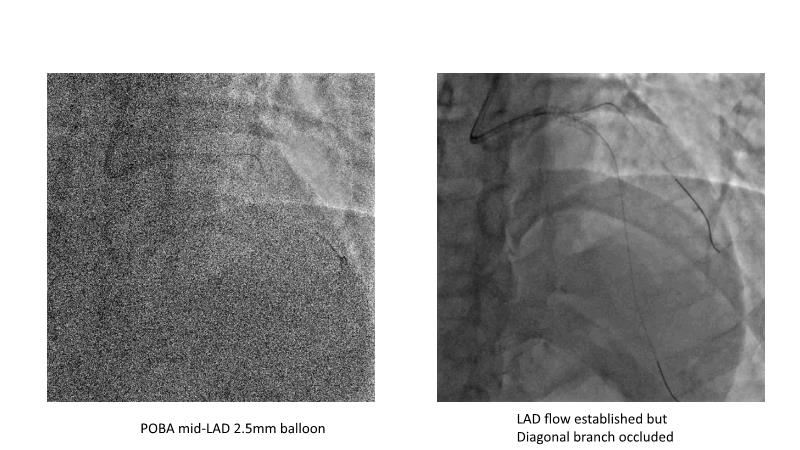

This session is recommended for you if you are seeking insights into the advantages of using IVUS imaging over visual assessment for better outcomes in left main bifurcation procedures. Discuss with experts the benefits of using RotaCUT in lesion preparation for left main bifurcation and explore the impact of high radial strength stents on the procedure's success.

• To see advantages of RotaCUT as part of lesion preparation in left main bifurcation

• To know how a high radial strength stent can make a difference in left main bifurcation